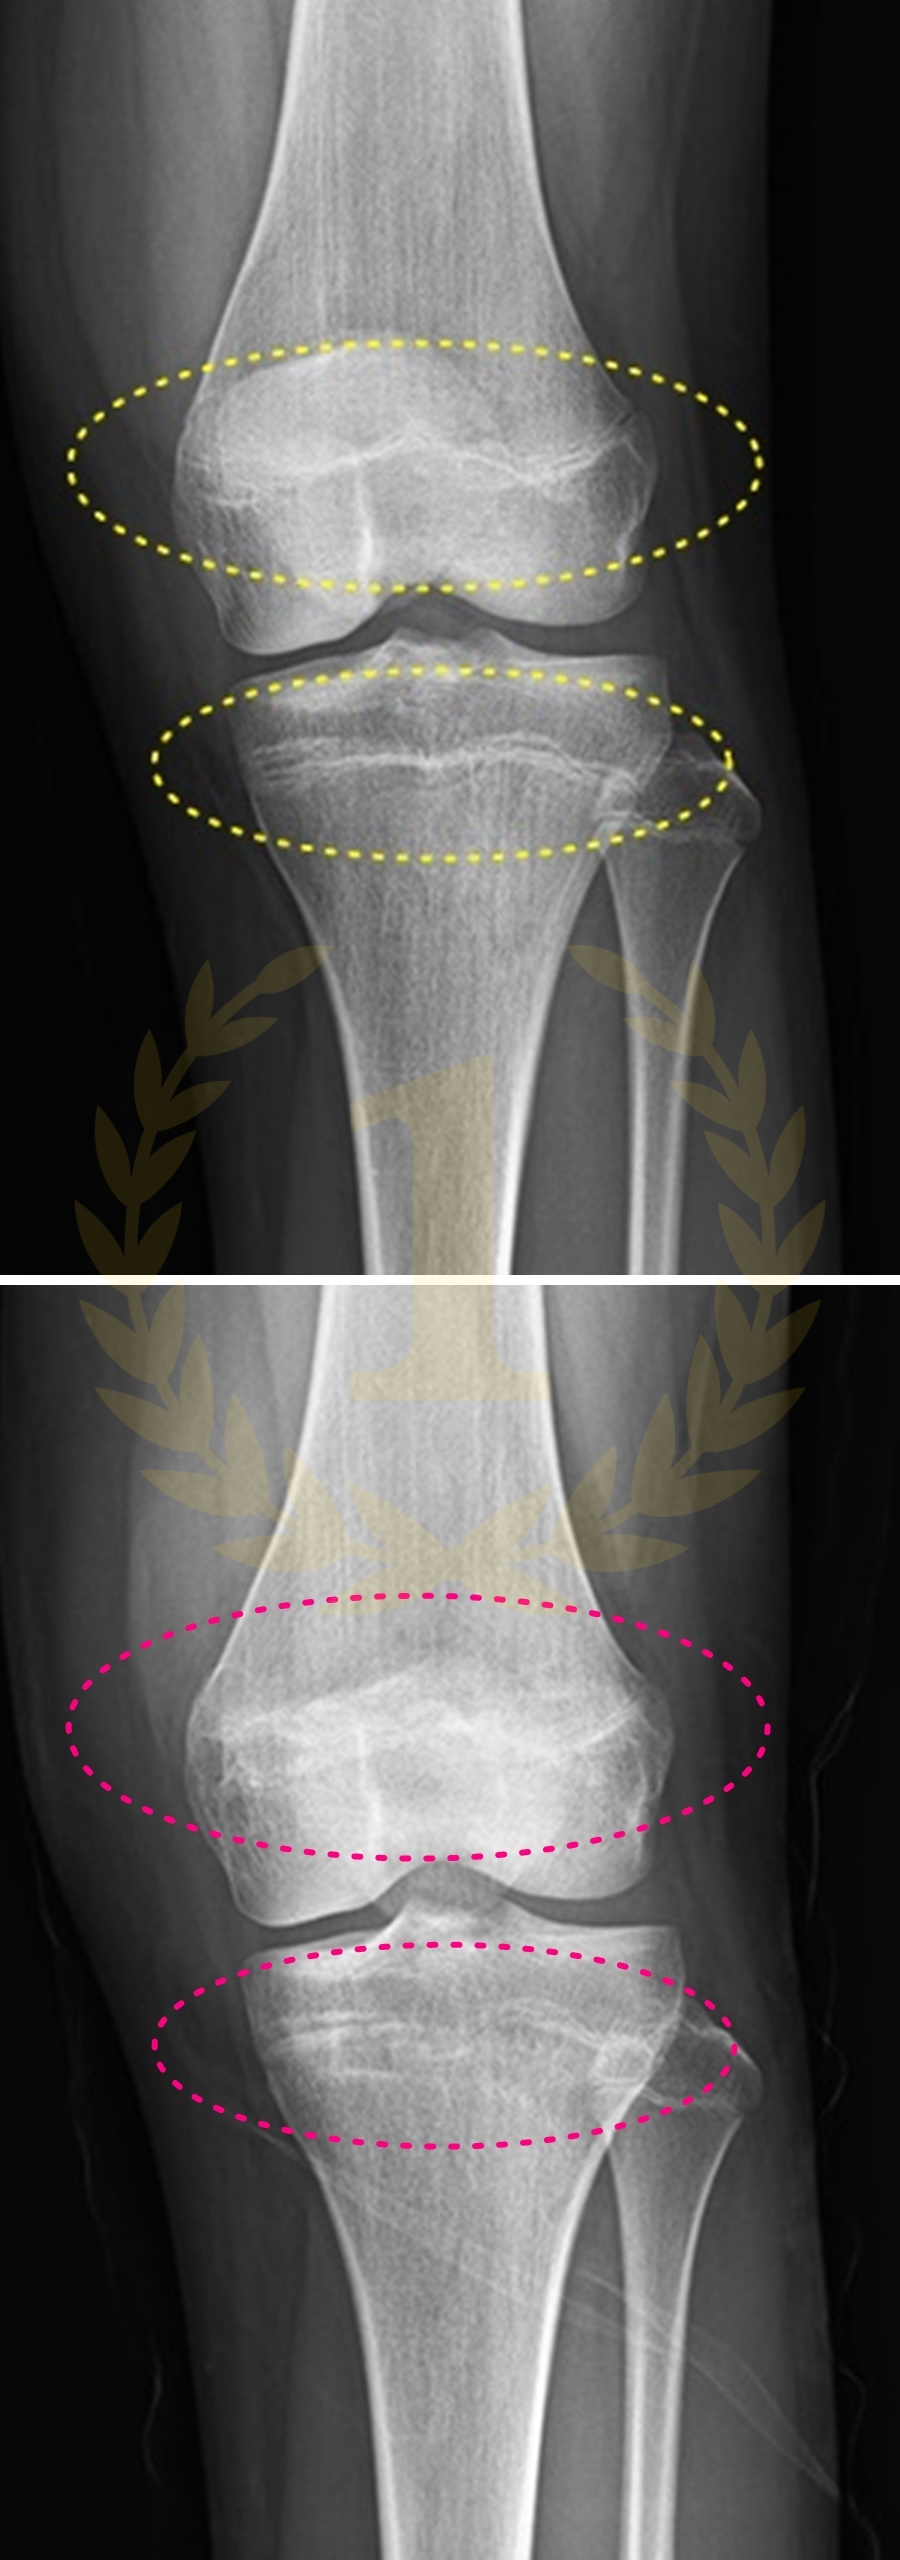

사지연장 및 변형교정

키수술ㅣ휜팔다리ㅣ휜손발가락ㅣ단지증ㅣ장지증

무지외반증ㅣ까치발ㅣ요족ㅣ족하수ㅣ소아마비